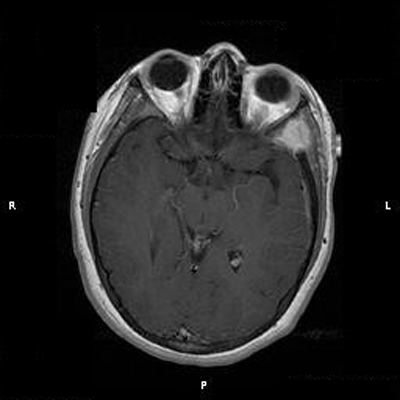

Clinical information: The patient was a 13 year-old girl who presented with worsening headache and some difficulties with memory, concentration and attention. MRI studies disclosed a 2.1 x 1.9 x 1.8 cm enhancing mass in the left temporal bone and sphenoid wing. The mass extended intracranially and abuts the left temporal bone accompanied by dural enhancement at that location. There is also extension through the bone into the submuscular temporal region. The following photos are taken from representative regions of the lesion. Panel 1 and 2 are CT scans at soft tissue and bone density respectively. Panel 3 and 4 are T1 weighed images without and with contrast respectively. Pandl 5 is proton density image. Panel A to D are cytologic (squash) prepartion for intra-operative consultation. Panel E and F are frozen sections for intraoperative consultation. Panel G to L are paraffin embedded sections.

The skin and bone are the most commonly affected organs but practically no organs are spared. The craniofacial bones and trunk bones are most commonly affected. The cranial base involvement may extend into the brain and involve the hypothalamus. The classic clinical triad of bony defects with exophthalmos and diabetes insipidus can be seen. The humerus and femur are less commonly involved. Small bones of the hands and feet are rarely affected. Radiologically, they occur as sharply demarcated, “punched out” osteolytic, usually intramedullary and rarely intracortical lesions. A thin sclerotic rim can be seen in some cases. Periosteal bone formation is usually not present. The lesion is usually small and about 1-2 cm in greatest dimension. Larger lesions may erode through the cortical bone and involve the adjacent non-osseous tissue as illustrated in this case.